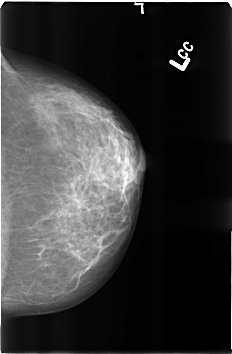

B_3360_1.LEFT_CC

LEFT_MLO LINES 4568 PIXELS_PER_LINE 3000 BITS_PER_PIXEL 12 RESOLUTION 50 NON_OVERLAY